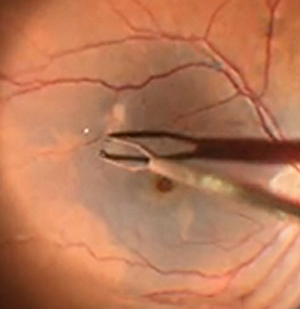

Vitreoretinal surgery is a highly specialized field of ophthalmology dealing with diseases of the retina and vitreous — the innermost structures of the eye responsible for vision. Dr. Tekchandani performs advanced procedures such as pars plana vitrectomy, scleral buckling, and macular hole surgery to restore and preserve sight.

Retinopathy of Prematurity is a condition affecting premature babies, leading to abnormal blood vessel growth in the retina. Dr. Tekchandani offers comprehensive ROP management, including laser photocoagulation, intravitreal injections, and surgical treatment for advanced stages.